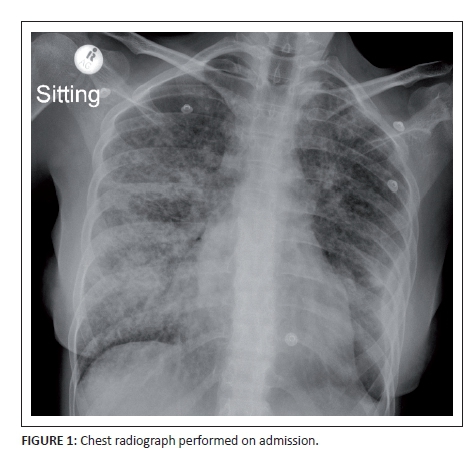

The chest X-ray (Figure 1) performed on admission demonstrated a reticulonodular pattern of lung field opacification with areas of coalescent consolidation. Right paratracheal and hilar lymphadenopathy was noted as well as a shallow left lower mid-zone surface convexity pleural reaction. Wasting of the soft tissues was indicative of chronicity or systemic disease.